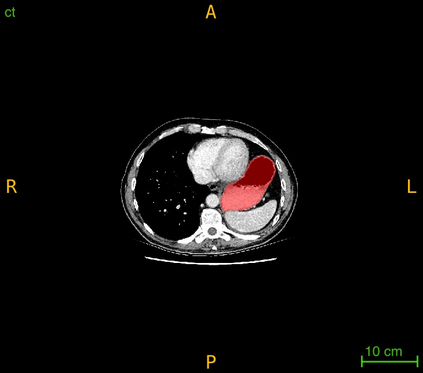

Interactive segmentation, an integration of AI algorithms and human expertise, premises to improve the accuracy and efficiency of curating large-scale, detailed-annotated datasets in healthcare. Human experts revise the annotations predicted by AI, and in turn, AI improves its predictions by learning from these revised annotations. This interactive process continues to enhance the quality of annotations until no major revision is needed from experts. The key challenge is how to leverage AI predicted and expert revised annotations to iteratively improve the AI. Two problems arise: (1) The risk of catastrophic forgetting--the AI tends to forget the previously learned classes if it is only retrained using the expert revised classes. (2) Computational inefficiency when retraining the AI using both AI predicted and expert revised annotations; moreover, given the dominant AI predicted annotations in the dataset, the contribution of newly revised annotations--often account for a very small fraction--to the AI training remains marginal. This paper proposes Continual Tuning to address the problems from two perspectives: network design and data reuse. Firstly, we design a shared network for all classes followed by class-specific networks dedicated to individual classes. To mitigate forgetting, we freeze the shared network for previously learned classes and only update the class-specific network for revised classes. Secondly, we reuse a small fraction of data with previous annotations to avoid over-computing. The selection of such data relies on the importance estimate of each data. The importance score is computed by combining the uncertainty and consistency of AI predictions. Our experiments demonstrate that Continual Tuning achieves a speed 16x greater than repeatedly training AI from scratch without compromising the performance.